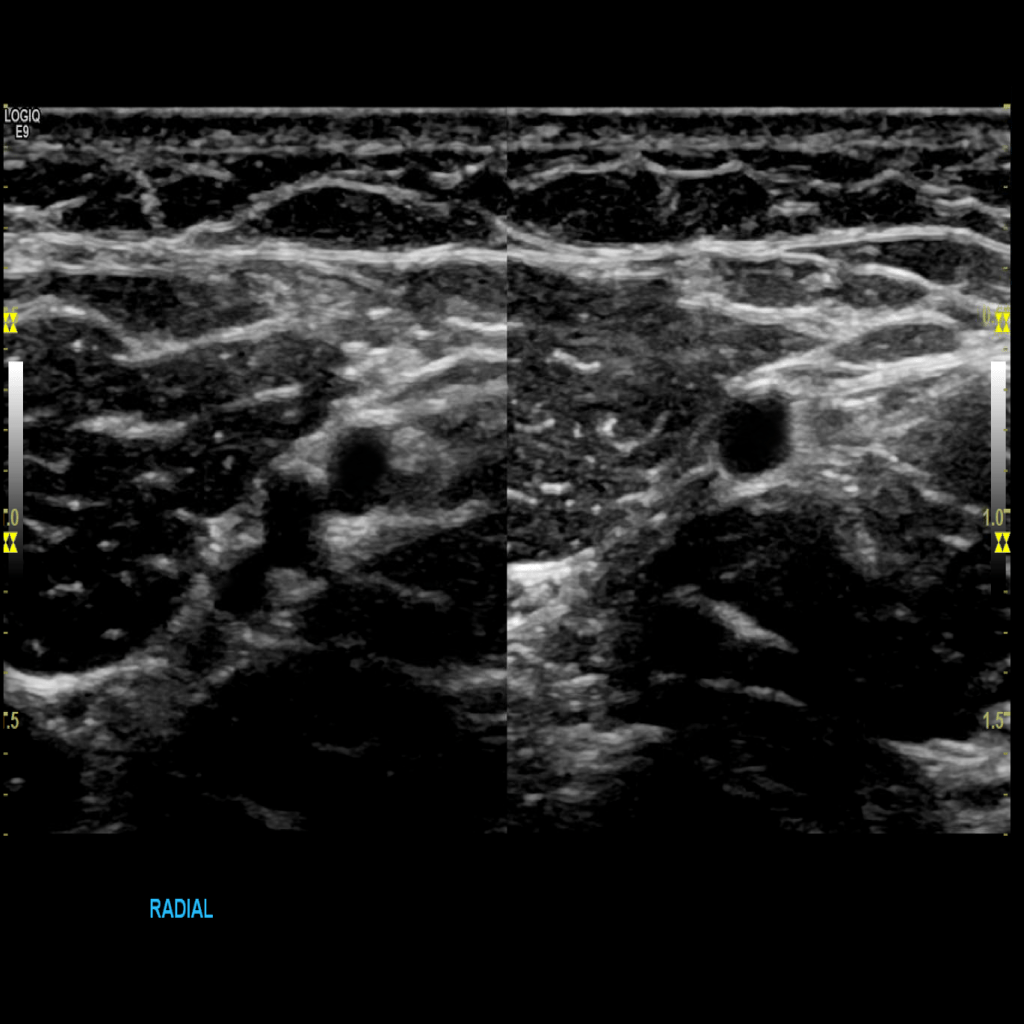

Scan the radial veins in grey scale, compression, color doppler and spectral doppler

Thrombus of the right basilic vein